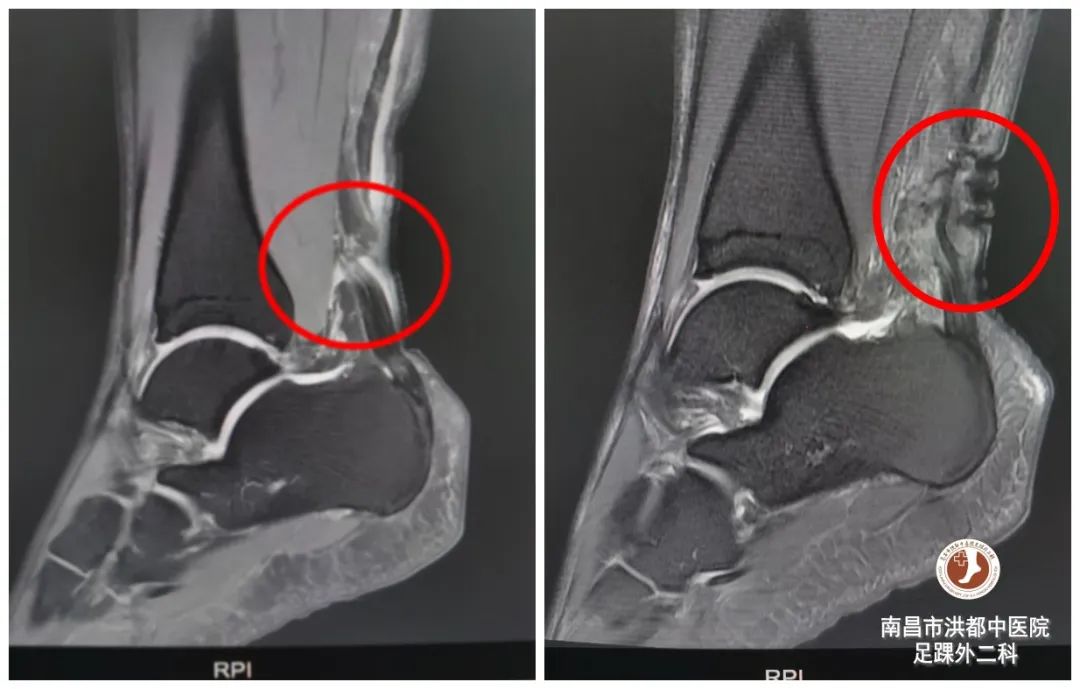

术前术后影像对比

经过一系列相关检查,确诊其 右足跟腱断裂, 并收治入院。7月11日上午,在腰硬联合麻醉下,邓雄伟足踝团队为患者进行了“ 跟腱断裂微创吻合术 ”,手术时长约30分钟,术中顺利,术后予预防感染、止痛消肿等对症治疗,并行石膏脱固定患肢,维持跟腱稳定。